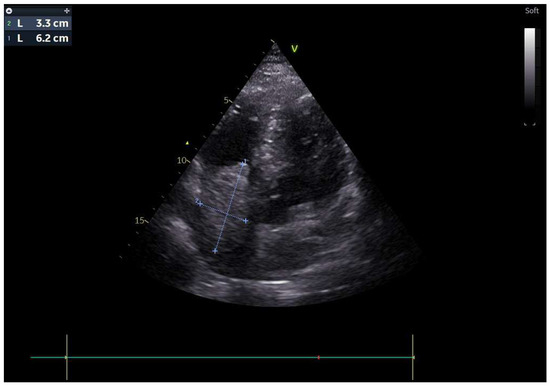

A 51-year-old male patient presented to our clinic in December 2023 with fatigue, abdominal distension and leg edema, which started three weeks prior. He had no history of chronic disease. On physical examination, dullness in the abdomen upon percussion, suggestive of fluid, was observed. Additionally, there were decreased breath sounds in the basals of the lungs, a tachycardic heart rhythm, and significant pretibial edema. The electrocardiogram (ECG) was consistent with sinus tachycardia. The patient’s blood pressure was 130/90 mmHg. Laboratory tests revealed hemoglobin: 13.2 g/dL; fasting blood glucose: 95 mg/dL; serum creatinine 1.2 mg/dL; aspartate aminotransferase (AST) 49 U/L; alanine aminotransferase (ALT): 46 U/L; bilirubin: 0.69 mg/dL; albumin: 3.6 g/dL; carcinoembryonic antigen (CEA): 43 ng/mL; and carbohydrate antigen (CA) 19-9: 361 U/mL. Electrolyte levels were within normal limits. Urinalysis showed proteinuria of 0.4 g/day. Paracentesis revealed a serum-to-ascites albumin gradient greater than 1.1 g/dL. Cytological examination of the fluid revealed benign cytological findings. TTE revealed a lesion 6.2 × 3.3 cm in diameter, suggestive of a low-moving hypoechoic thrombus or mass (Figure 1). This lesion almost completely filled the right atrium and stuck to the tricuspid valve. Dilation of the inferior vena cava and severe insufficiency of the tricuspid valve were also observed. A work-up was started to differentiate heart failure and a possible cardiac mass. Thorax CT showed multiple nodules in the lung and a suspicious mass in the right atrium. A PET scan showed that there was segmental wall thickening at the stomach and esophagogastric junction, measuring 7.5 cm in size and showing 18-FDG uptake with an SUV max of 22.4, which was evaluated in favor of primary malignancy. Multiple metastatic lymphadenopathy in the abdomen, free fluid in the abdominopelvic region, metastatic lesions in the liver and lung and supraclavicular lymphadenopathy were detected (Figure 2). The lesion seen on TTE was evaluated as a tumoral thrombus suspicious lesion with dimensions of 8.8 × 5.5 cm at the level of the right atrium on PET-CT and a maximum standard unit value (SUVmax) of 12.8. Cardiac magnetic resonance imaging (CMRI) was planned to differentiate the tumor/thrombus, but it could not be performed because the patient could not tolerate lying flat. Cardiology and surgery opinions were obtained, and close follow-up with anticoagulant treatment was recommended. An ulcerovegetating mass was detected in the upper-GI endoscopic evaluation. Histopathological evaluation of the biopsy specimen was consistent with gastric adenocarcinoma. PD-L1 IHC was conducted using a Ventana Dako anti-human PD-L1 mouse monoclonal antibody, clone 22C3, with a positive control. PD-L1 protein expression was assessed using the CPS and found to be positive, with a value of 15. HER-2 status was evaluated by both IHC and silver in situ hybridization (SISH). For IHC, Ventana anti-HER-2/neu rabbit monoclonal antibody clone: 4B5 was employed with a positive control. SISH was performed on a Ventana Benchmark Ultra fully automated system using the inform HER-2 dual in situ hybridization DNA probe cocktail with positive and negative controls. The HER-2 IHC score was +3, and SISH demonstrated HER-2 gene amplification with a HER-2/CEP17 ratio ≥ 2 (positive).

Figure 1. Transthoracic echocardiography (TTE) showed of a low-moving hypoechoic thrombus or mass.